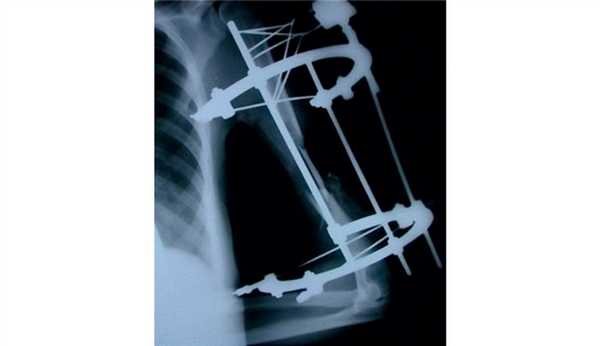

На рис. 3-9 Рис. 3. Пациентка И., 34 лет. Внешний вид до операции. Рис. 9. Внешний вид и функция через год после операции. представлены все этапы обследования и лечения пациентки И.

Рис. 4. Рентгенограмма пациентки И. до операции.

Рис. 5. Пациентка И. Этапное оперативное вмешательство. а — замещение дефекта плечевой кости цементным спейсером; б — транспозиция торакодорсального лоскута в область мягкотканного дефекта плеча; в — послеоперационная рентгенограмма.

Рис. 6. Рентгенограммы пациентки И. после удаления цементного спейсера.